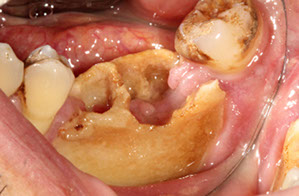

Dentigerous cyst

Dentigerous cyst lined b thin layer of stratified squames c chronic inflam in stroma